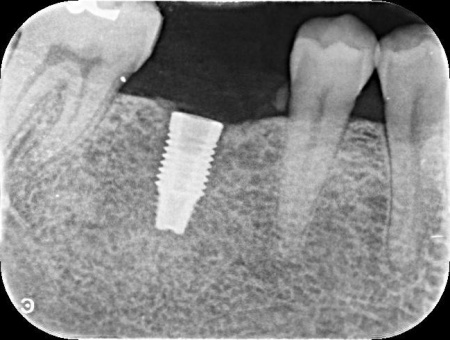

治療中

| 行ったご提案・治療内容 | 患者様はあごの骨に人工歯根を埋め、その上に人工歯を装着するインプラント治療を希望されています。 インプラント治療は自分の歯のような自然な見た目と噛み心地が期待できる一方で、自費診療のため費用が高くなることや外科処置を伴うため身体的負担がかかること、治療期間が比較的長くなる点がデメリットです。 また、安定したインプラント治療を行うためにはインプラントを支えられるあごの骨が残っているか、インプラントの上に人工歯を取り付けた際に噛み合わせの歯が邪魔をしないかなどを確認する必要があります。 その結果、十分な骨の量があり、噛み合わせの歯もインプラントを入れた際に自然に噛める位置に生えていたため、インプラント治療を行う条件は問題ないと判断しました。 【治療手順】 最後に見た目や噛み合わせに問題がないことを確認し、治療を終了しました。 |